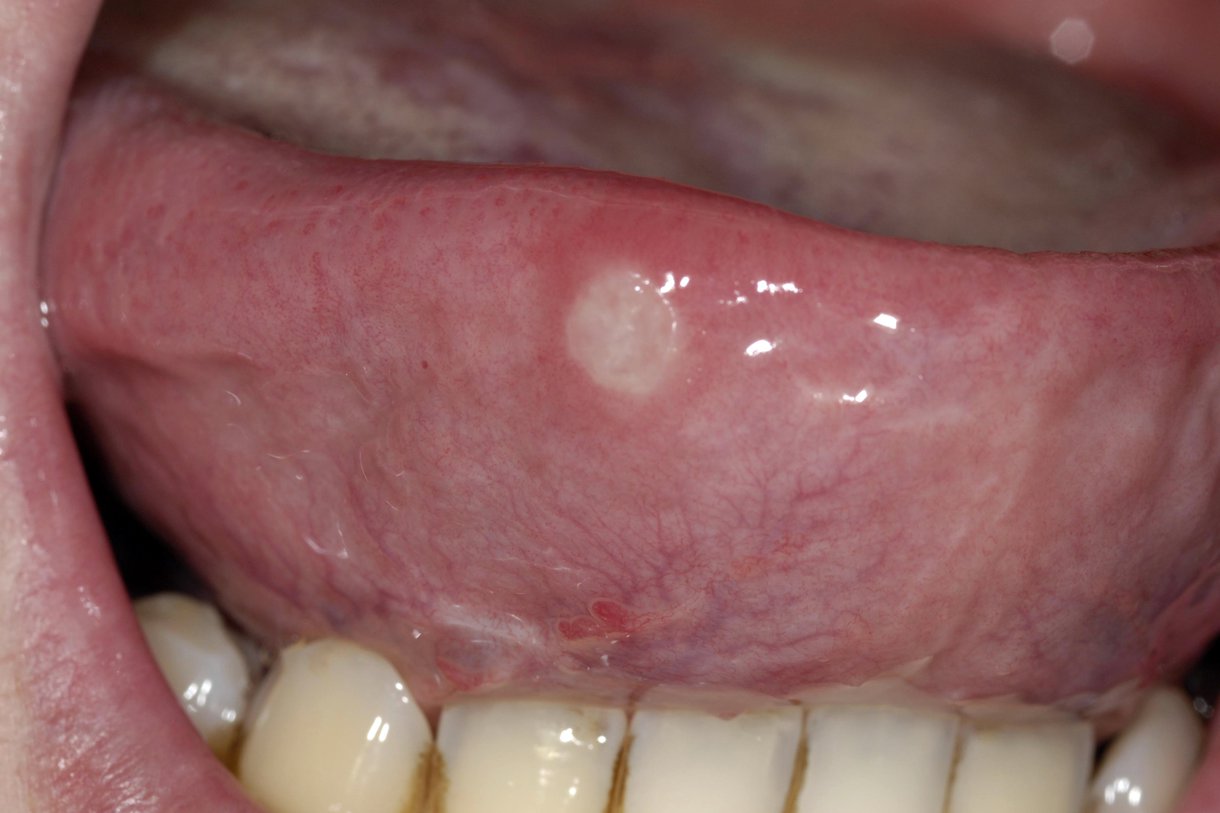

علاج قرحة اللسان عند الكبار

تقرحات اللسان ماذا تفعل عند الإصابة بها ويب طب

ما سبب تقرحات اللسان موضوع

أسباب تقرحات اللسان وطرق علاجها سوبر ماما

ما أسباب تقرحات اللسان موضوع